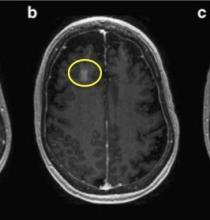

What's the Blood-Brain Barrier & How Do You Cross It?

The brain has evolved a method of protecting itself called the blood-brain barrier. But the BBB can backfire when it prevents drugs to treat brain diseases – for example, a malignant brain tumor – from reaching the site of the disease. Science has come up with some clever methods for defeating the brain's own defenses.